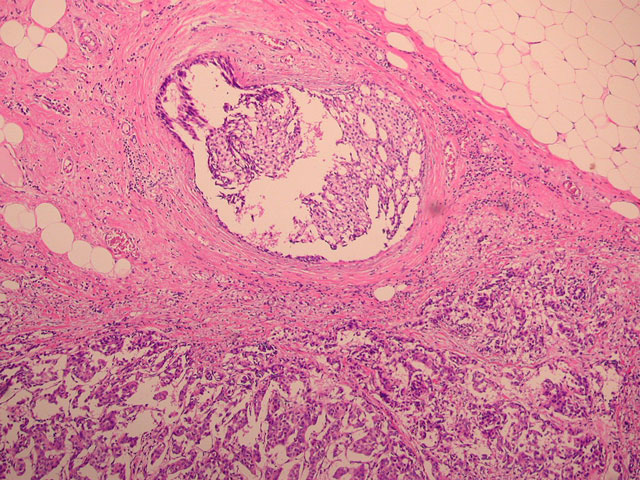

DCIS‚ƐZ•”